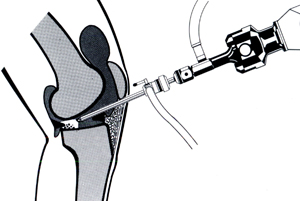

Якщо такі епізоди повторюються, виникає необхідність в операції з видалення розірваної частини меніска. Це нескладна і безпечна операція, яку виконують через проколи шкіри під контролем артроскопа - тонкого оптоволоконного зонда діаметром близько 0,5 см, до якого приєднані відеокамера і джерело світла.

Під контролем відеозображення на моніторі відірвану частину меніска відсікають і видаляють.

Після операції вже через кілька годин можна вставати на оперовану ногу, на наступний день - повернутися додому, а через 10-14 днів - виходити на роботу. Після видалення частини меніска функція коліна відновлюється повністю - можна займатися фізичною працею, спортом.